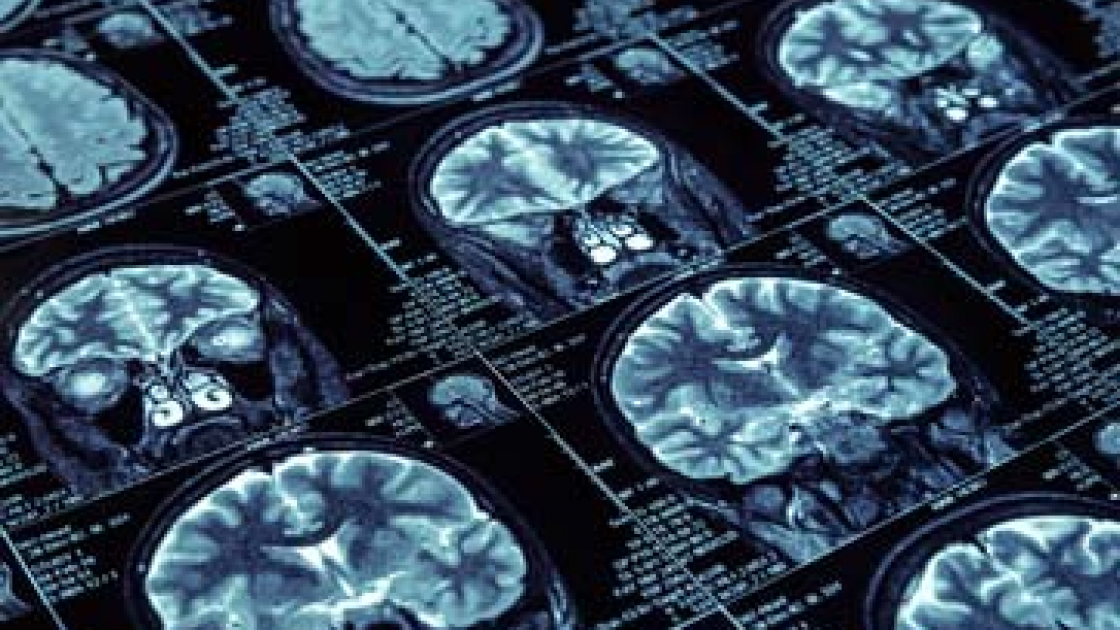

L’annuncio – dato con un articolo pubblicato sulla piattaforma elettronica arXiv lo scorso 9 settembre e firmato, oltre che da Marianna La Rocca, da un gruppo di suoi colleghi dell’università barese – ha suscitato notevole interesse nella comunità scientifica internazionale, per una serie di motivi che vedremo tra poco. Occorre precisare subito, tuttavia, che l’algoritmo non è ancora utilizzabile in fase clinica. Marianna La Rocca ha messo a punto un algoritmo capace di apprendere: un classico, ormai, dell’Intelligenza Artificiale. In questo caso è capace di apprendere come distinguere il cervello di una persona sana da quello di un malato di Alzheimer, fosse anche in uno stadio molto precoce, comparando le immagini raccolte con la Risonanza Magnetica Nucleare (RMI). La fase di “apprendimento” ha comportato l’analisi comparata, da parte dell’algoritmo, delle immagini RMI di 67 cervelli: 38 di Alzheimer e 29 di persone sane.

La fase successiva è stata quella di mettere alla prova la bravura del sistema di intelligenza artificiale. L’algoritmo ha dovuto analizzare le immagini RMI di 148 cervelli: 52 di persone sane, 48 di malati di Alzheimer e 48 di persone con problemi di memoria che tempo dopo (anche nove anni) hanno sviluppato l’Alzheimer. I risultati sono stati davvero importanti: l’algoritmo ha riconosciuto nell’86% dei casi un cervello malato da un cervello sano. Ma, soprattutto, ha individuato nell’84% dei casi i cervelli con Alzheimer incipiente. In pratica, se la tecnica funzionerà, sarà capace di dare non solo una mano nella diagnosi della malattia neurodegenerativa ma potrà funzionare anche nella diagnosi ultraprecoce. Ovvero, capire quando un cervello sta per sviluppare una malattia, l’Alzheimer, che diventerà conclamata anche dieci anni dopo.